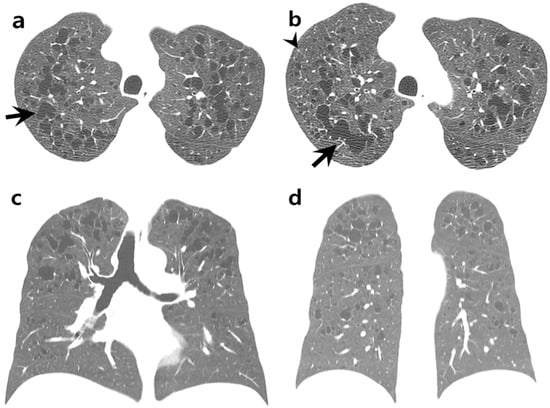

A chest CT scan revealed multiple pulmonary cysts of variable sizes and shapes (Figure 1a–d). The intervening lungs were clear. Cysts were mainly distributed in the peribronchial areas of upper and middle lung zones. Both basal lungs, including costophrenic angles, were relatively spared. Some small round cysts showed rarely perceptive walls, consistent with emphysema. However, most cysts showed irregular, branched, or bizarre shapes with well-defined walls. A few micronodules were observed in the periphery of both upper lobes. Therefore, PLCH of the predominantly cystic type was suspected. A video-assisted thoracoscopic wedge biopsy was performed from the right upper lobe.

Figure 1.

A 34-year-old male with intermittent cough and chest tightness. (a,b) Axial chest CT images with lung window setting showing cysts of variable sizes in both upper lungs. Intervening lungs are clear. Most cysts show prominent walls with branched, lobulated, or bizarre shapes (arrows). A few micronodules are observed in the periphery of the right upper lobe (arrowhead in (b)). (c,d) Coronal chest CT images showing distribution of cysts, predominantly in the upper and middle lung zones. Both basal lungs and costophrenic angles are relatively spared. (e) Resected lung tissue showing cystically dilated space with hyalinized fibrosis (arrows) (×10, Hematoxylin and Eosin staining). Two small nodular areas with stellate cell aggregation are marked with circles. (f) Pigmented macrophages with finely granular cytoplasm are accumulated in distal and peribronchiolar airspace. There is no definite diffuse interstitial thickening or inflammation (×400, Hematoxylin and Eosin staining). (g) Magnification view of an irregular cyst (star in Figure 1e) showing thickened cystic wall with fibrotic change (×100, Hematoxylin and Eosin staining). (h) Magnification view of a small nodular area marked in Figure 1e showing stellate cell aggregation (×400, Hematoxylin and Eosin staining). (i,j) Only a few stellate cells showed positive expression for CD1a (i: ×200, j: ×400). Note presence of anthracotic pigmentation (arrow in Figure 1i) nearby.